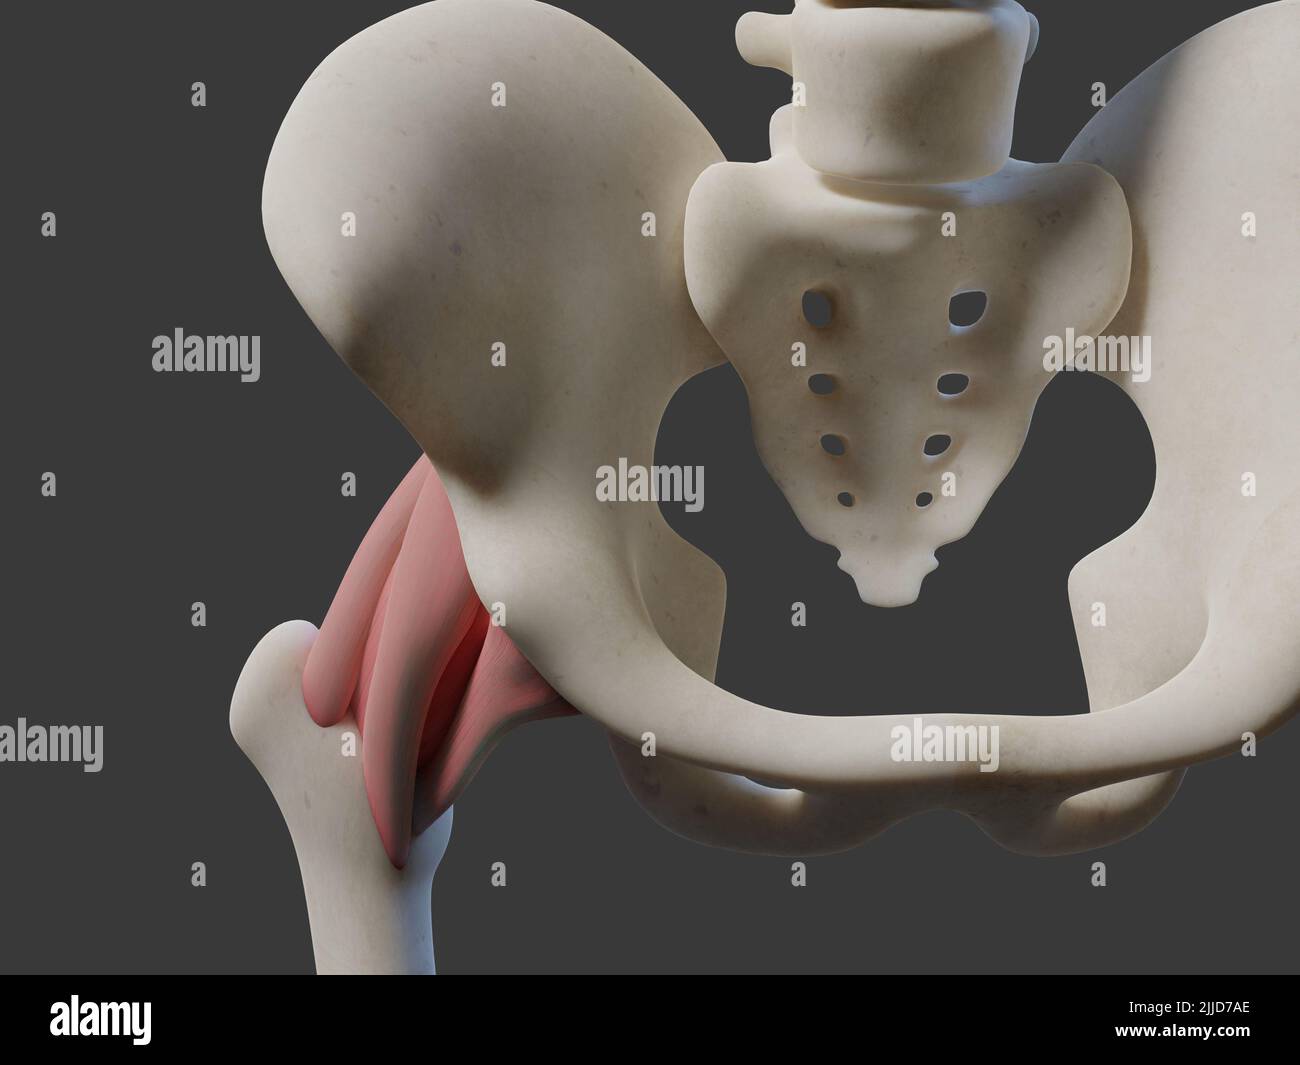

3D illustration of human joint. Includes Stock Photohttps://www.alamy.com/image-license-details/?v=1https://www.alamy.com/3d-illustration-of-human-joint-includes-image476034902.html

3D illustration of human joint. Includes Stock Photohttps://www.alamy.com/image-license-details/?v=1https://www.alamy.com/3d-illustration-of-human-joint-includes-image476034902.htmlRF2JJD7AE–3D illustration of human joint. Includes